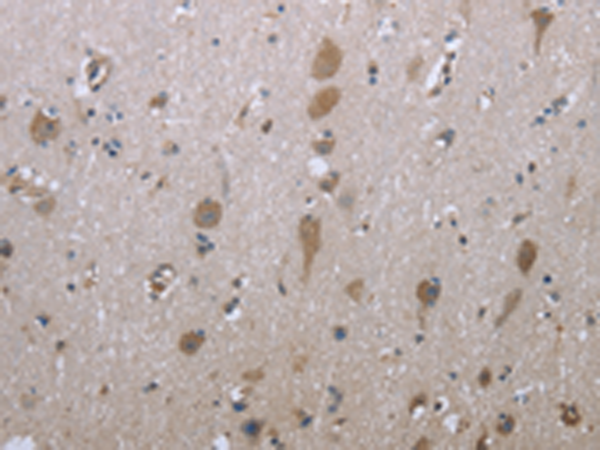

IHC positive control: |

Human brain |

IHC Recommend dilution: |

50-100 |